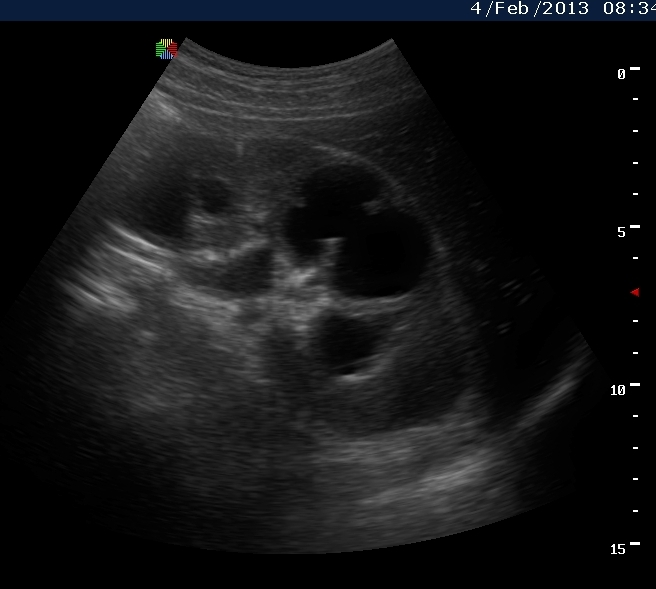

Вот как выглядит почка при первом осмотре и в феврале

Видим длительно существующий гидронефроз вследствие процесса в области лоханочно-мочеточникового сегмента (видео 1), с утолщением стенок ЧЛС и истончением паренхимы почки - наиболее частая причина у взрослых - туберкулез.